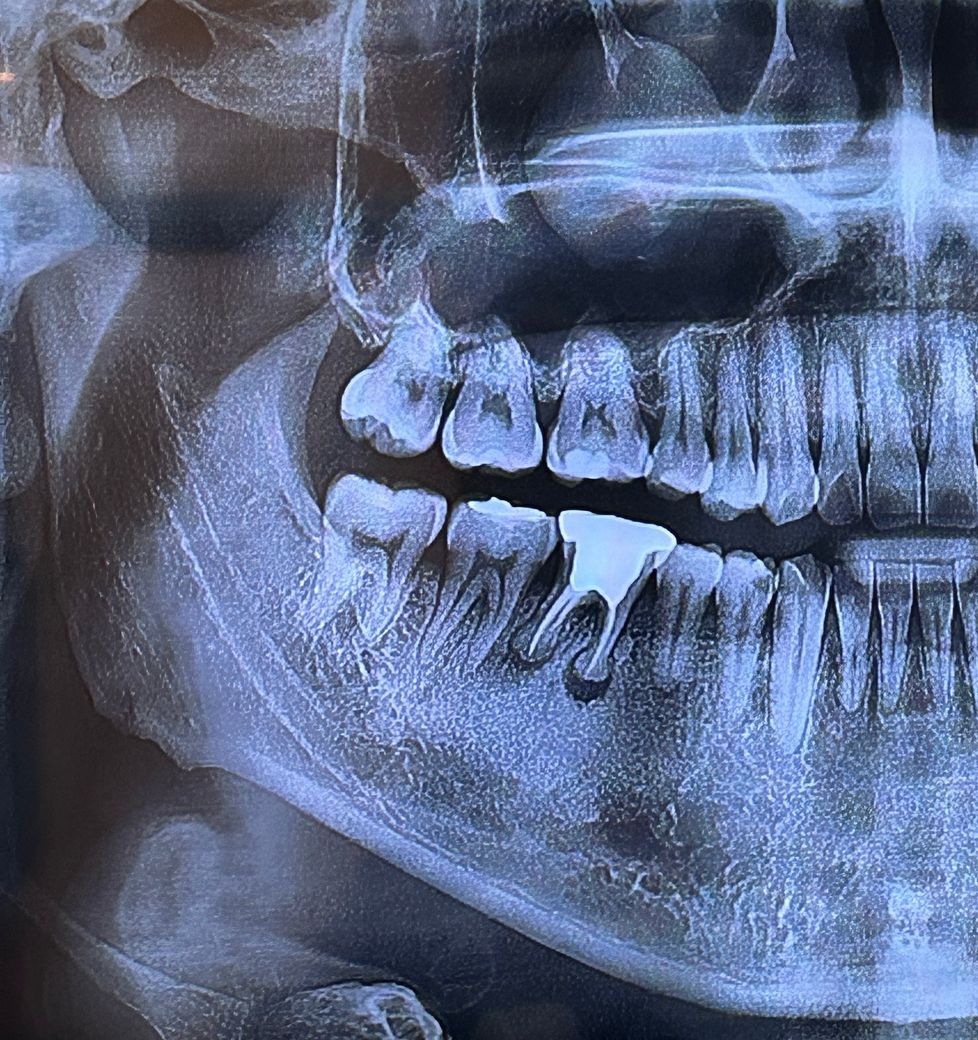

오늘 임플란트 수술+뼈이식 받았는데요

잘된걸까요? 다음3달이후에는 다시 수술할필요가앖이 바로 머리올린다고 하시네요

• 2번 째 사진

1. 임플란트 뿌리를 심은 후(1차 수술)에 임플란트 뿌리가 뼈에 붙을 때까지 뚜껑을 닫아두는데 두 종류가 있습니다. 그 중에 2차 수술을 진행하지 않아도 되는 타입(힐링 어버트먼트)을 달아둔 상태입니다. 3달 후 다시 수술할 필요가 없다는 것은 그걸 의미하고요.